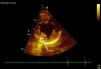

Miocardiopatia no compactada presentándose como ictus de repetición

Non-compacted cardiomyopathy, presenting as repeated stroke